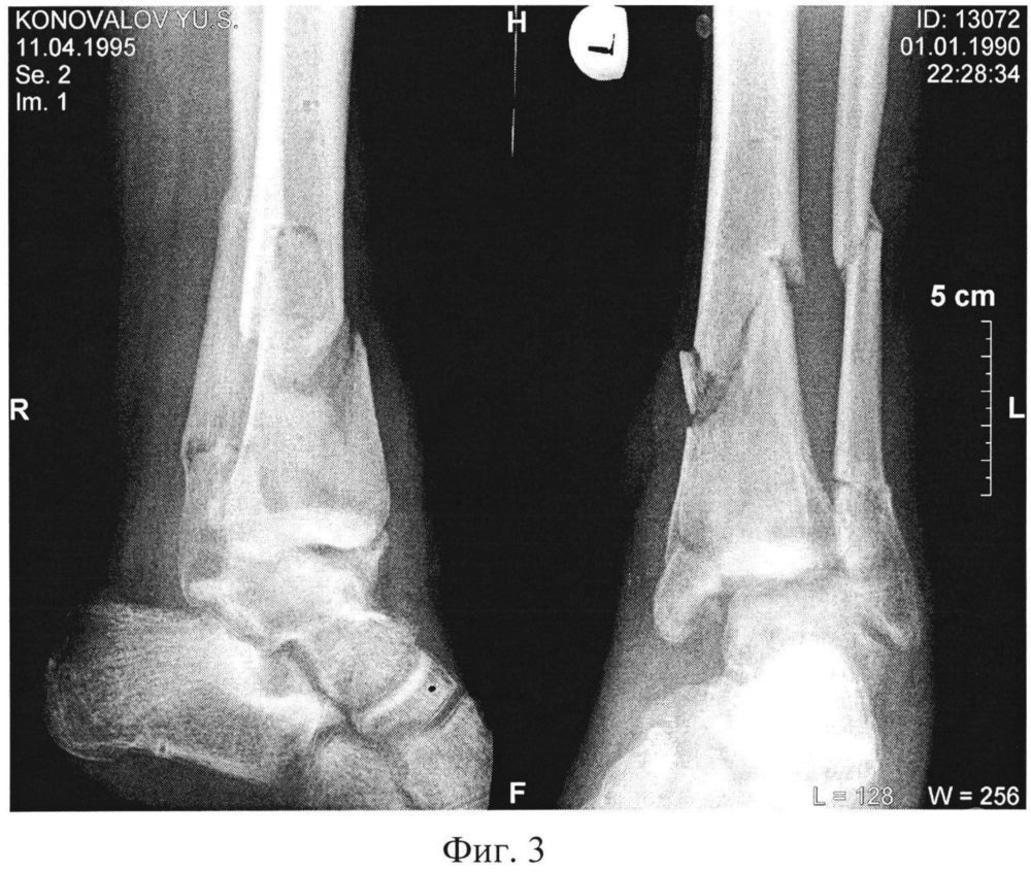

Без консолидации перелома

Без консолидации перелома 119 фото